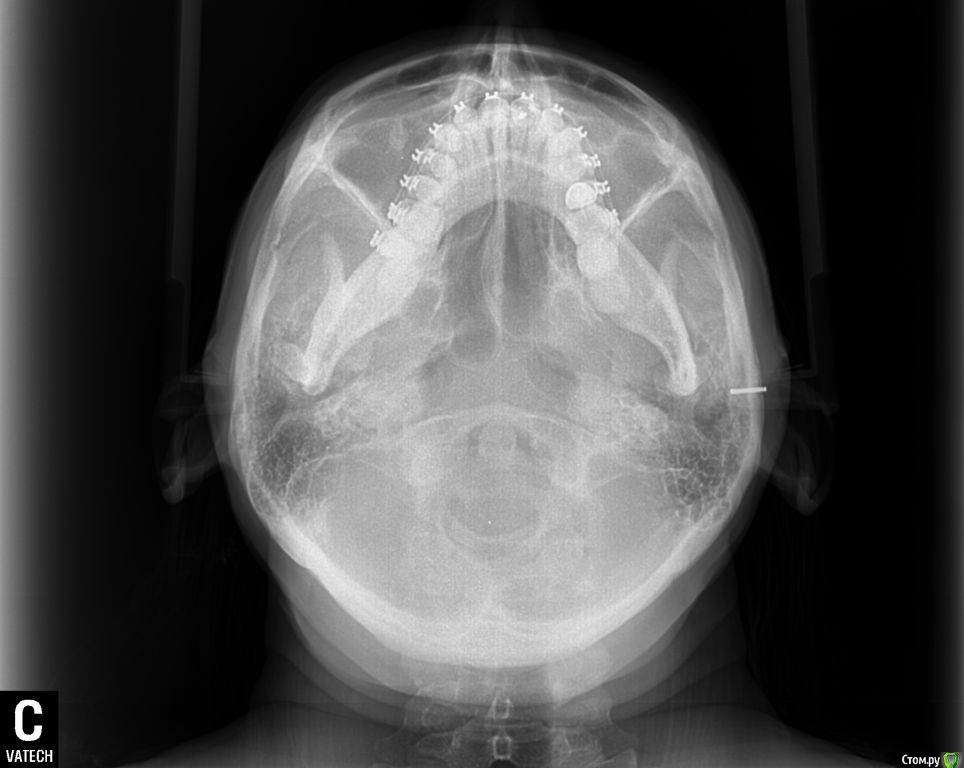

ol"ga Опубликовано 15 августа, 2015 Поделиться Опубликовано 15 августа, 2015 (изменено) Здравствуйте, Уважаемые Доктора!Очень нуждаюсь в вашей помощи. Мне 35 лет, в октябре прошлого года была установлена частичная брекет-система : на верхней ( 6 зубах, от клыка до клыка) лингвальная брекет-система и нижней ( 9 зубах) вестибулярная брекет-система и были изготовлены окклюзионные накладки на боковых зубах нижней челюсти. Перед ортодонтическим лечением никаких снимков не делала. За первый месяц ношения лингвальных брекетов верхняя челюсть достаточно быстро выдвинулась вперед, результат меня устраивал, но в дальнейшие 5 месяцев челюсть все продолжала выдвигаться вперед, в результате в прикусе впереди образовалась щель между челюстями в 5-7 мм, нижняя челюсть не так быстро успевала выдвигаться вперед, заметила что я неосознанно выдвигаю нижнюю челюсть пытаясь подстроиться под верхнюю, но речь была свистящая, шипящая, жевала на правую сторону, т.к. на левую было неудобно (по ощущениям, слева окклюзионная накладка была ниже, чем справа). Так проходила 6 мес., результат меня не устраивал, верхние зубки оставались кривыми, стали выпирать клыки, врач сказал, что это от давления дуги, а верхняя челюсть сильно выдвинулась вперед и стала похожа на открытый прикус. Мой врач сказал, что положения кривых наклонов зубов лингвальные брекеты не исправляют, а выставляют зубки в ряд, и предложил бесплатно поменять на вестибулярную брекет-систему. В конце апреля сделали панорамный снимок, трг в боковой проекции и переустановили брекет-систему на все зубки верхней челюсти, и на нижней кроме 7-к и 8-к, убрали окклюзионные накладки, но челюсть у меня не сомкнулась в привычном положении, заметила, что зубки на нижних шестерках, где были накладки, как бы просели в десну. Врач сказал, что это временно, все выровняется. Первую неделю зубки болели обычно как после активации аппарата, затем появилась боль в районе правого сустава, сначала после приема пищи, жевать я продолжала на правую сторону, пыталась приловчиться, куда удобнее, а затем боли продолжались и в покое, несколько раз просыпалась ночью от боли, пила нимесил. В этом остром периоде заметила асимметрию лица, по ощущениям нижняя челюсть «съехала» вправо, сомкнуть челюсть в таком положение не могла, сильная боль была, я ее сдвигала влево, получался перекрестный прикус (это было спустя 3 недели после установки брекет-системы). Обратилась к своему ортодонту, он сказал, что челюсть перестраивается под правильное положение зубов, могут быть боли, а асимметрию он не видит. Боли продолжались. Челюсть я так и не могла сомкнуть в « правильном» положении. Обратилась в другую клинику к ортодонту, поставили дисфункцию ВНЧС, 2 раза делала миорелаксацию с интервалом месяц (в конце мая и июня), рекомендовали не нагружать сустав и широко не открывать рот, все это я соблюдала, ела только только на левую сторону (до сих пор на нее и жую), острая боль постепенно сменилась просто дискомфортом в области правого сустава. После первой процедуры миорелаксации на второй день я смогла без боли сомкнуть челюсть в « правильном» положении, но комфортнее было ее держать в расслабленном состоянии, чуть левее, в основном я так и ходила. В это время я заметила, что у меня верхняя челюсть сместилась вправо, верхний левый зубной ряд начал мешать языку в его привычном положении, все зубки на обеих челюстях как бы наклонились в сторону языка, создалось впечатление, что челюсть сузилась. Еще постоянно царапал край дуги на верхней правой 7-е, мне ее 2 раза подпиливали и убирали щипцами, но через несколько дней опять край вылазил и накалывал щеку, решили вообще убрать замок с правой 7-и т.к. на щеке постояна была незаживающая язва от этой травмы. На днях соскочила дуга с левой верхней 7-и. Но врач сказал, что это невозможно, что воспалительный процесс в суставе он снял и я могу обратиться к своему ортодонту для продолжения ортодонтического лечения. Я обращалась еще к 5 специалистам специалистам. Никто проблемы не видит. один из специалистов в результате обследовал сделал оттиски зубов и дал заключение: Диагноз : Миофасциальный болевой синдром лица с дисфункцией височно-нижнечелюстного сустава. Дислокация диска с вправлением в левом ВНЧС.(вентральная). Бруксизм. Другой предложил шину на нижнюю челюсть, но только после снятия брекетов с нижней челюсти.Продолжаю поиски. Сделала трг в прямой, боковой и подбородочно- теменной проекции, кт обеих суставов, ищу специалистов которые могут мне помочь в моей проблеме, но в моем городе это проблема. Бруксизма за собой не замечала, родные тоже, зубами не скреплю, во сне не жую, но 100% утверждать не могу. Проблем с ВНЧС никогда не было, ни щелчков, ни хруста, ничего. На данный момент иногда поднывает в области правого сустава, а в основном чувство дискомфорта в нем. Уважаемые Доктора, подскажите, пожалуйста, как в моем случае должен проходить план лечения, можно ли исправить асимметрию лица, можно ли вернуть верхнюю челюсть на место и почему врачи не видят этой проблемы, очень нуждаюсь в вашей помощи, хочется вернуть свое лицо и функциональность внчс. Эпикриз.doc Изменено 15 августа, 2015 пользователем ol"ga Ссылка на комментарий

Yana guapa Опубликовано 15 августа, 2015 Поделиться Опубликовано 15 августа, 2015 я не вижу у ВАс асимметрии лица, асимметрии верхней челюсти. А вот нижняя челюсть смещена влево, (это видно по ОПТГ и фото), вследствие чего произошло смещение дискав таких случаях обычно1. выравнивают зубные ряды ( с удалением восьмерок) 2. ставят нижнюю челюсть в правильное положение (различными способами, специальные пружины, эластики, форсус, твин форс и т.д.) каждый врач сам для себя выберает, что ему удобнее п.с. похоже что вверху слева ВАм удаляли восьмерку, нго оставили 1 корень. Ссылка на комментарий

Skip Опубликовано 24 августа, 2015 Поделиться Опубликовано 24 августа, 2015 Зубной ряд верхней челюсти СПРАВА выше, чем слева? Ссылка на комментарий